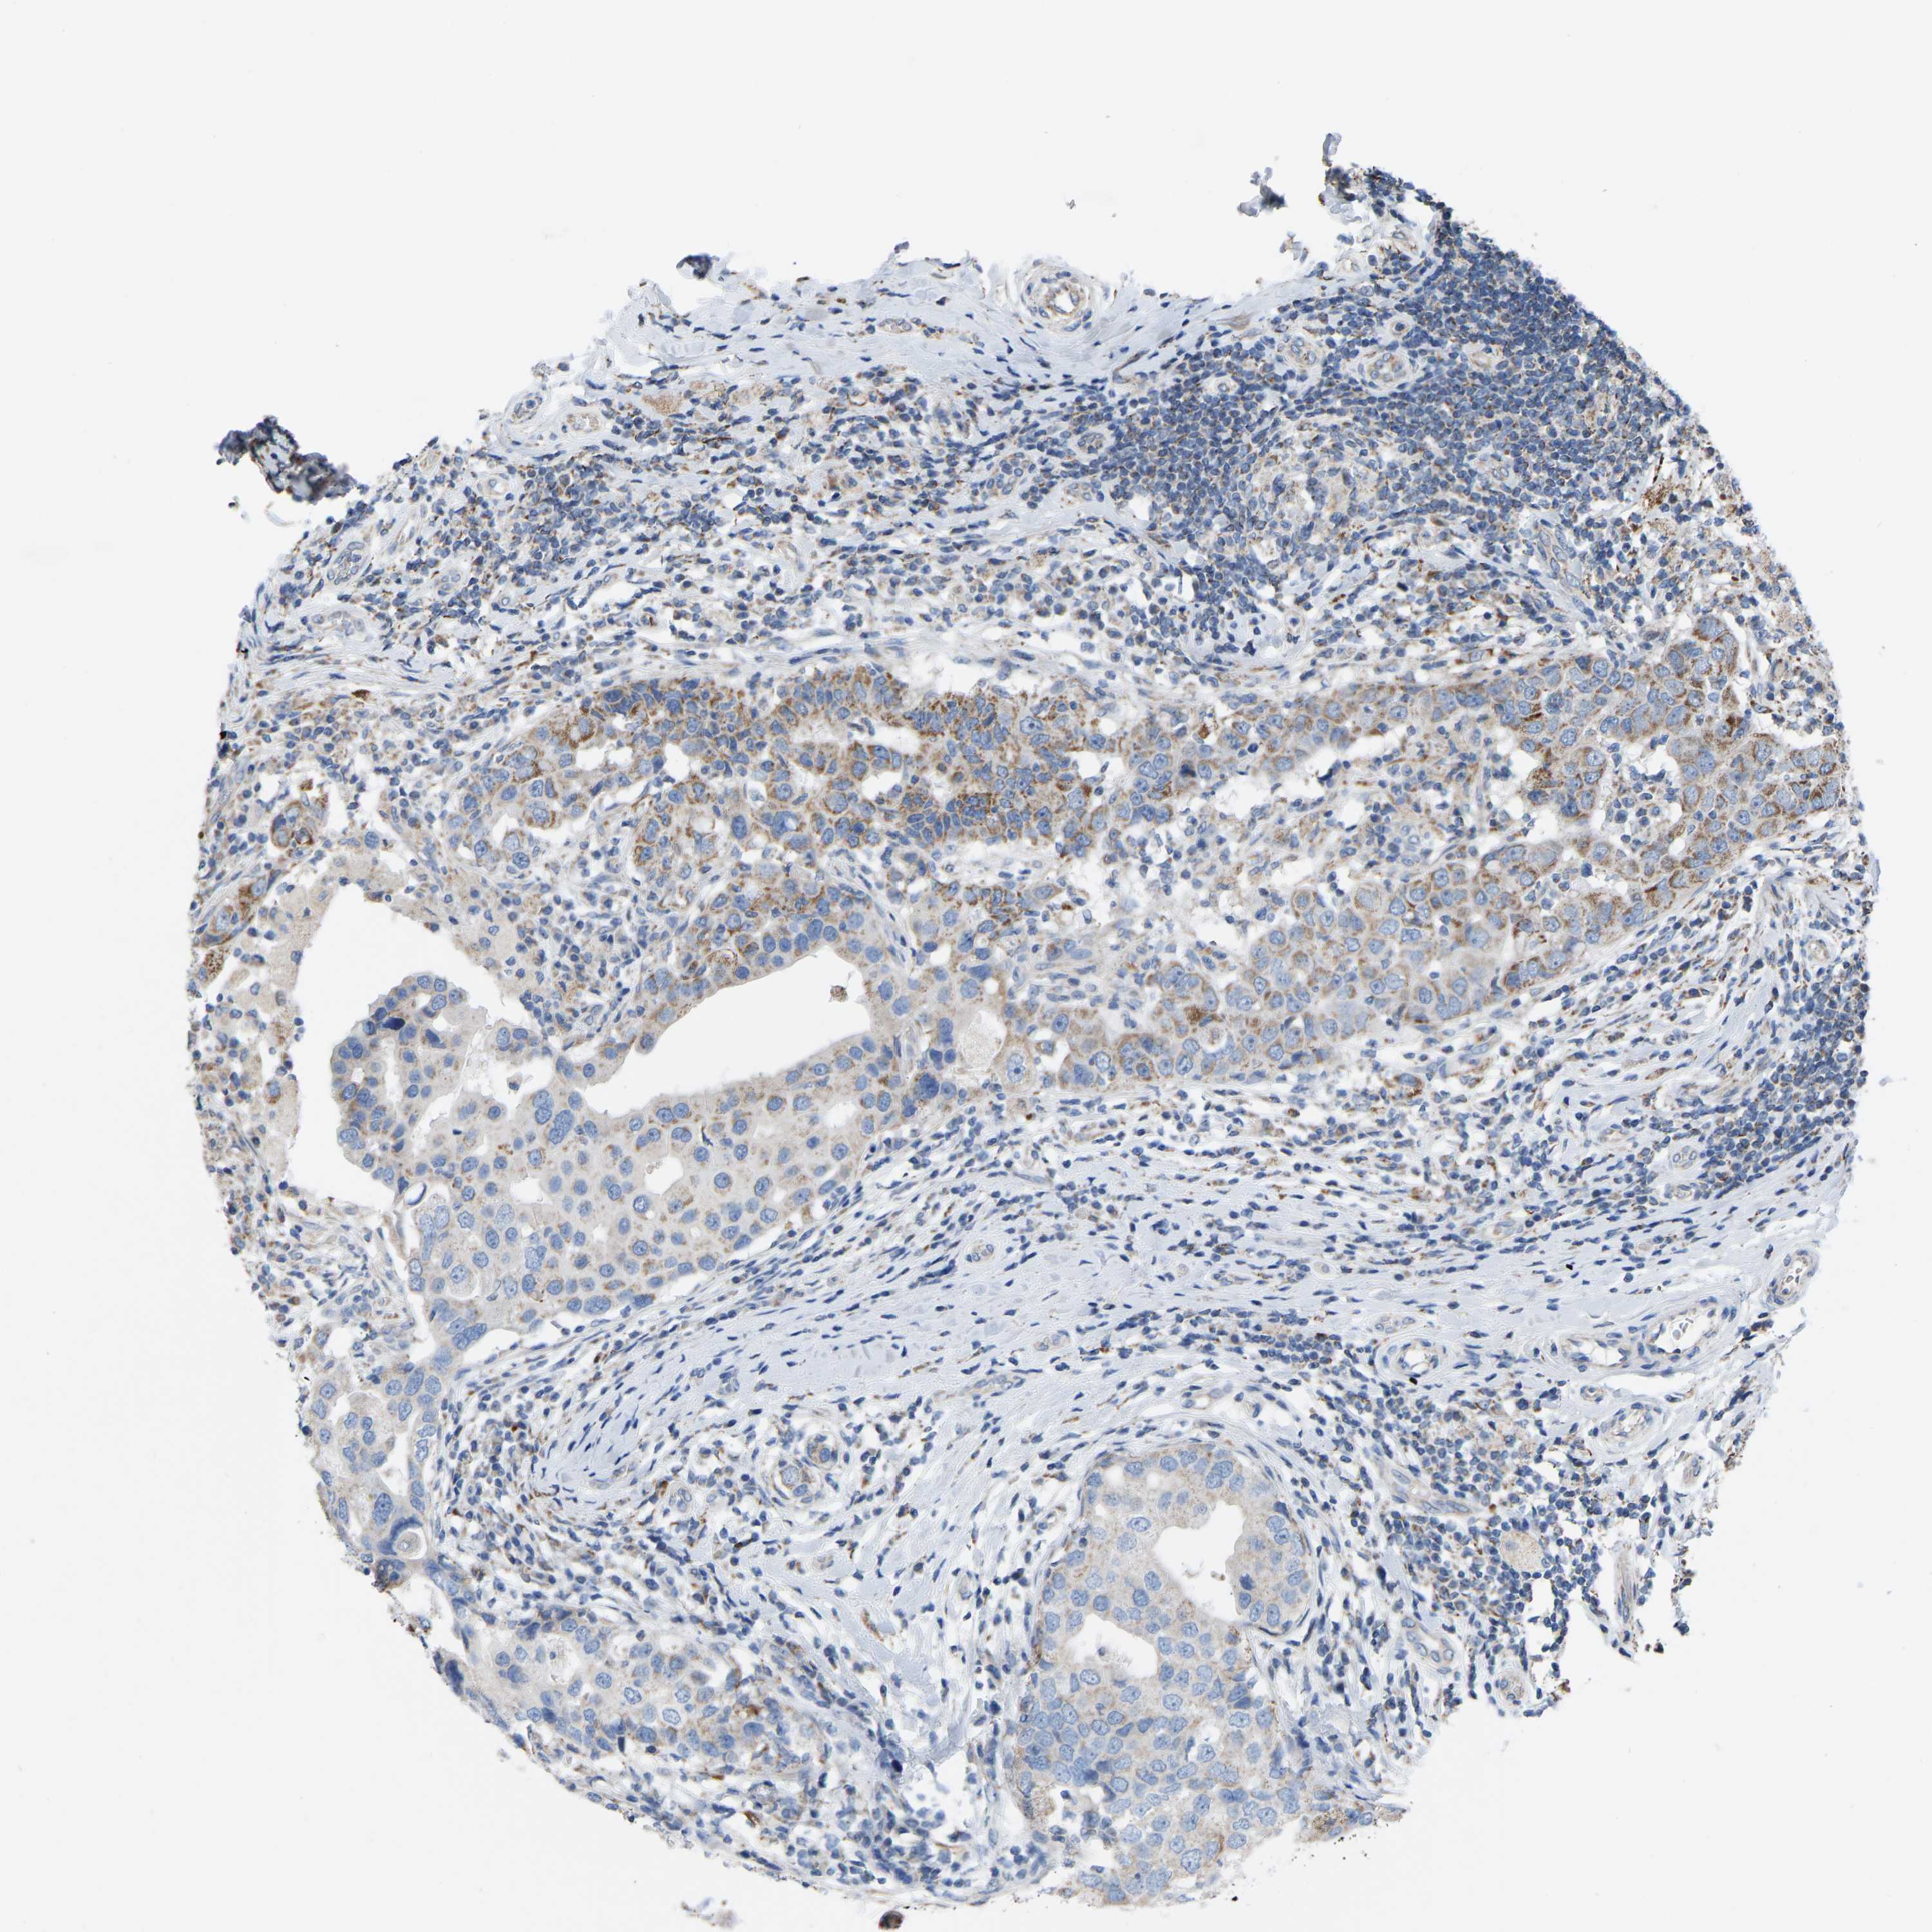

BRCA TCGA BRCA VALIDATION PROTEIN EXPRESSION

ANTIBODIES

AND

VALIDATION